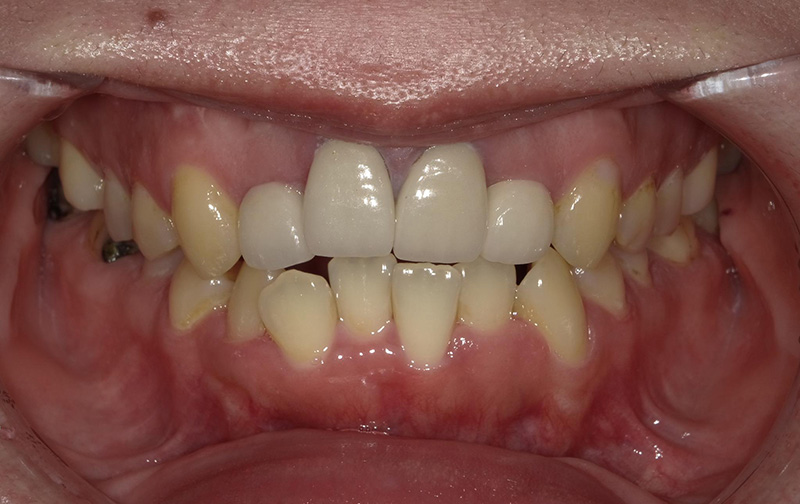

レントゲン、口腔内写真

セラミック治療を進めていく際には、患者様の目指しているゴールを明確にして、あとは根のコンディションがどうなのか?歯茎のコンディションはどうなのか?を考慮して、最終的なゴールを決めていきます。

確かに前歯2本とても長く作られてしまっていますね。

この状態だと大きく口を開けて笑う事も難しいですよね?